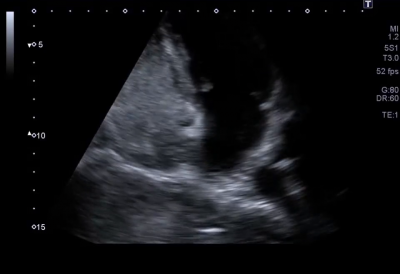

Cestou venafemoraliscommunis (VFC) byla provedena pravostranná katetrizace. Katétrem MPA 4F se však nedařilo projít skrze FOA, ani s podporou intrakardiální echokardiografie. V průběhu vyšetření byl proveden kontrolní bubble test, který neprokázal průnik bublin přes septum a levá síň se mohutně naplnila kontrastem s odstupem přibližně pěti sekund. Katetrizačně byloFOA vyloučeno, nicméně bylo vysloveno podezření na přítomnost klinicky významnýcharteriovenózních (AV) malformací. Pacientce byla nasazena acetylsalicylová kyselina (ASA) v kompromisní dávce a byla předána do péče hematologů. Dále sepacientce v rámci diferenciální diagnostiky doplnila CT angiografie arterie pulmonalis, kde byl nález vícečetných AV malformací v plicnímparenchymu oboustranně, největší vlevo v segmentu S5, vpravo v S4, ostatní menší (obr. 1, 2, video 1, 2).

TTE slouží jako rychlá, jednoduchá a minimálně invazivní metoda pro prvotní screening pAVM. Po intravenózním podání rozmíchaného fyziologického roztoku se v levých srdečních dutinách během dvou až pěti srdečních tepů snadno zviditelní echogennímikrobubliny, které naznačují potenciální existenci pravolevého plicního zkratu. Na rozdíl od přítomnosti intrakraniálního zkratu, při kterém jsou mikrobubliny přítomné v levostranných srdečních oddílech ihned po jejich aplikaci. Další zobrazovací metoda využívaná v diagnostice této anomálie je kontrastní CT vyšetření s tenkými řezy, které slouží k přesné identifikaci lokalizace (zda jde o mnohočetné diskrétní nebo difuzní), velikosti a typu (např. jednoduché versus komplexní) pAVM.7